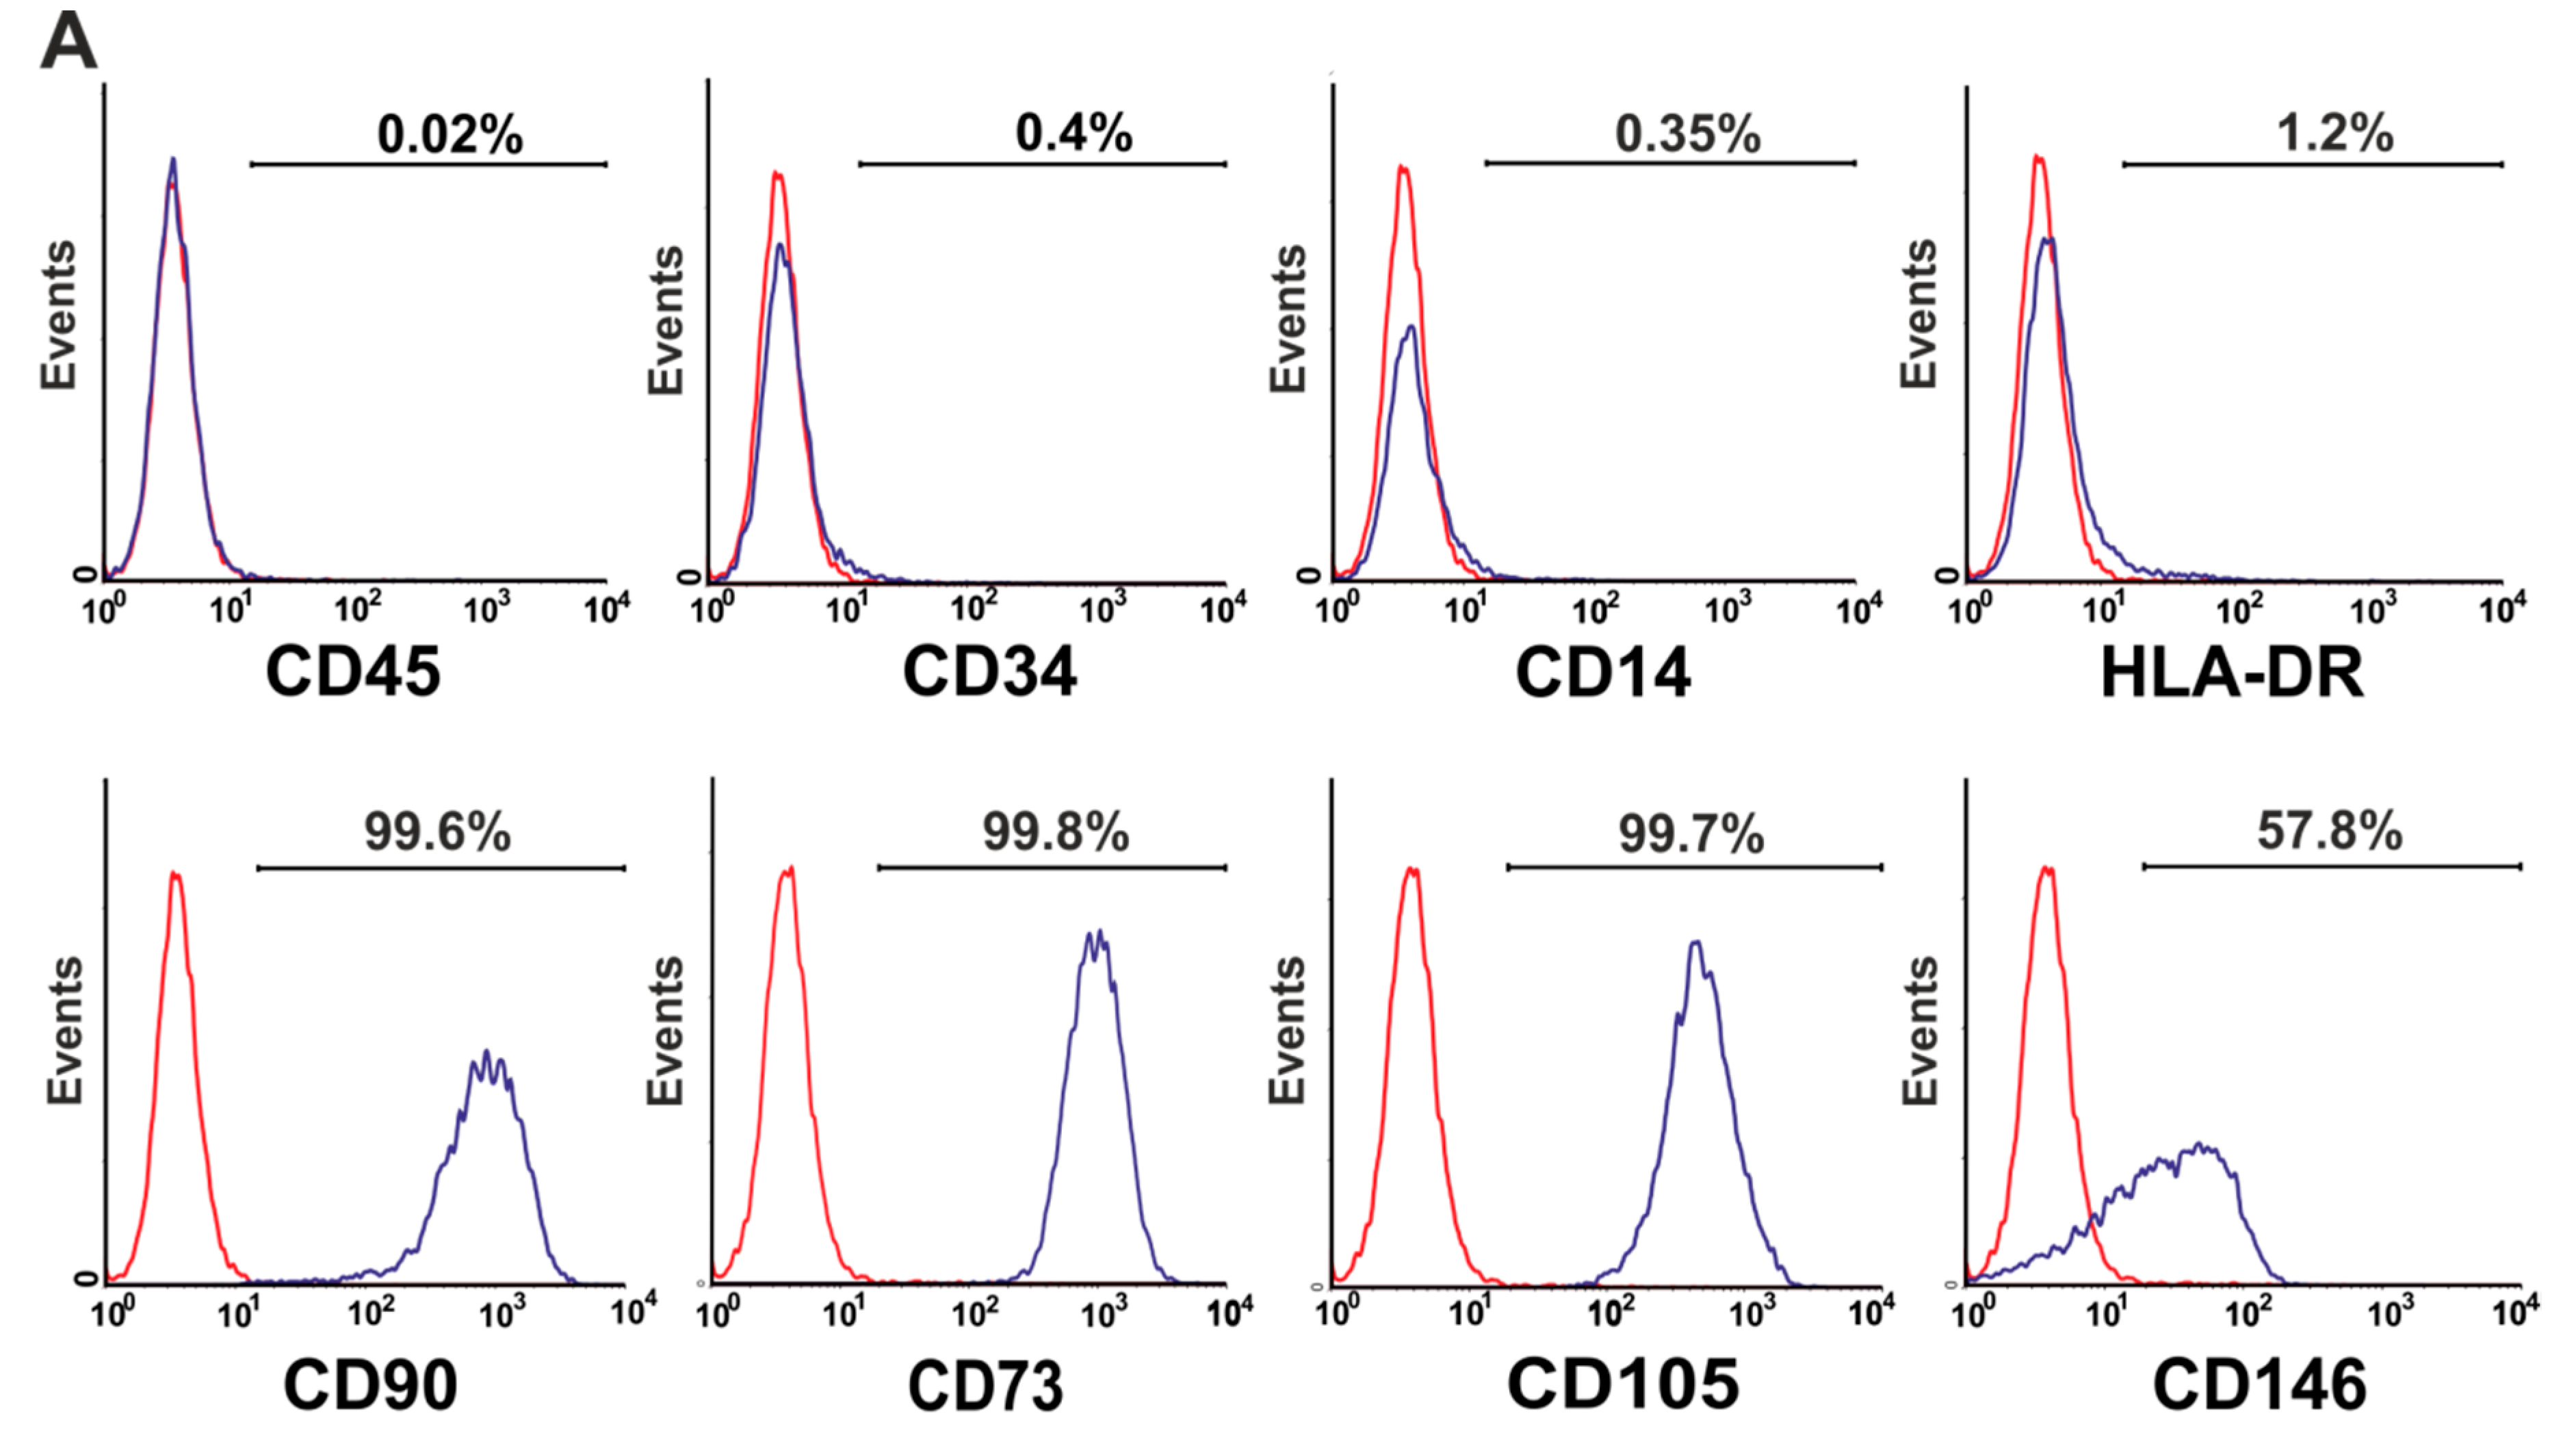

3.4. Phenotype of Mesenchymal Stromal Cells (MSCs) Generated by BM-MNCs of Patients with Non-Malignant Hematological Diseases (NMHD)